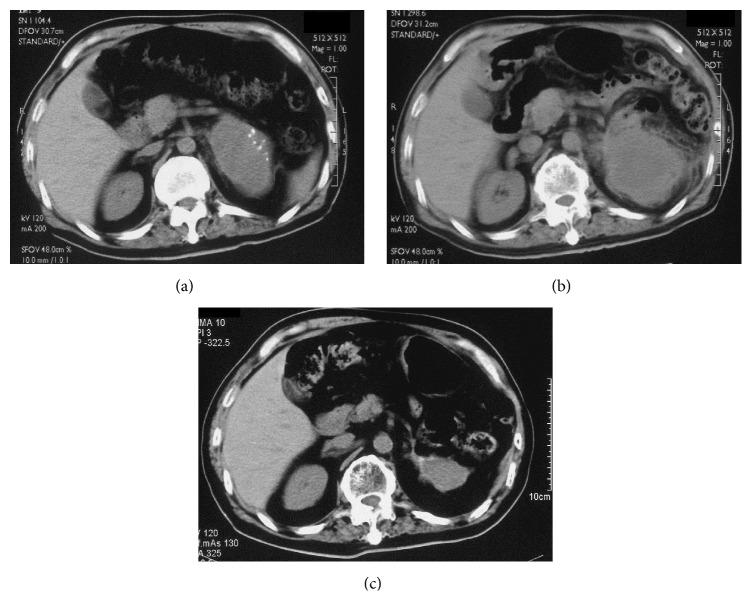

Here, we report the case of a 62-year-old man with neuroblastoma, which is extremely rare in adults. His tumor was resected, but it recurred four months later. Radiotherapy reduced tumor size, and the patient remained in good health three years after surgical tumor removal. The residual tumor and the treatments administered to this patient were evaluated. We have also reviewed the literature.